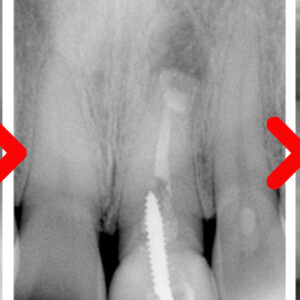

17. 수암동치과 신경관과 가까운 경우에도

수암동치과 신경관과 가까운 경우에도   안녕하세요. 모든 진료에 진심을 다하는 곳, 더플러스치과입니다. ​ 사랑니를 생각하면 공포감을 먼저 느끼는 분들이 많으실 텐데요.   주변의 경험담이나 본인이 겪은 발치 경험으로 좋지 않은 이미지를 떠올리게 됩니다.   사랑니는 영구치 중에서도 마지막에 맹출하며,   더보기…